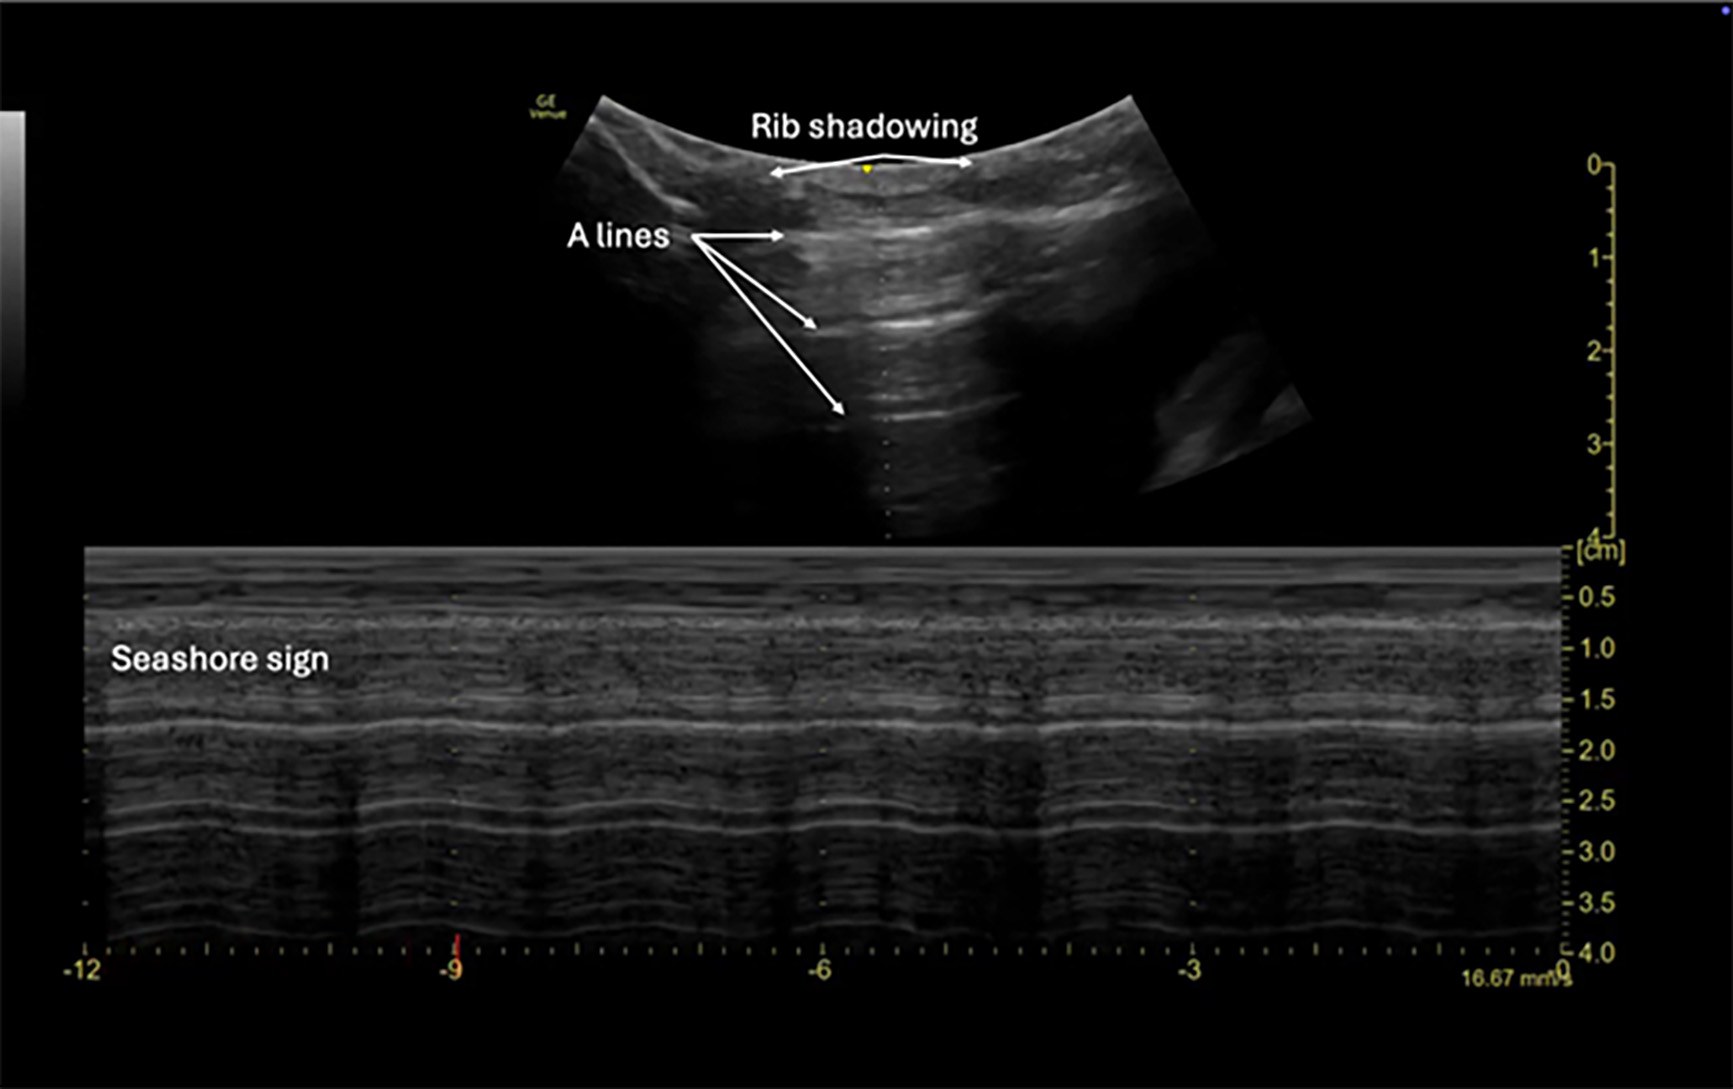

Lung View

The lung view in the E-FAST is obtained by placing a high-frequency linear probe or a phased array probe in the midclavicular line at the second or third intercostal space on the anterior chest wall, typically with the probe marker oriented toward the patient’s head. This view is used to rapidly evaluate for pneumothorax, hemothorax, or other causes of lung collapse. In pediatric patients, where chest wall compliance is higher and auscultation may be less reliable in noisy environments, lung ultrasound offers a highly sensitive and radiation-free method of assessment.40

The hallmark of a normal lung exam is the presence of lung sliding, which is the horizontal motion generated by the visceral and parietal pleura sliding against one another. This can be visualized in real-time (B-mode) or confirmed with M-mode, where normal lung movement produces the classic “seashore sign” (a granular pattern beneath a smooth superficial line). In the case of pneumothorax, lung sliding will be absent, and M-mode will instead reveal the “barcode sign” or “stratosphere sign,” indicating no pleural movement.42 In pediatric trauma patients, particularly when radiation exposure is a concern, lung ultrasound has demonstrated a sensitivity of up to 86% to 100% and specificity of 94% to 100% for pneumothorax when performed by trained operators.43 It also outperforms chest X-ray for the early detection of pneumothorax and pleural fluid in trauma settings.44

While lung sliding rules out pneumothorax in the scanned region, its absence is not specific and also may be seen in mainstem intubation, pleural adhesions, or apnea. To improve diagnostic accuracy, additional findings, such as the presence or absence of B-lines (comet tail artifacts) and the lung point (transition between sliding and non-sliding pleura), should be assessed since detection of the lung point is highly specific for pneumothorax.45

The use of lung views as part of the E-FAST exam is particularly valuable in children, where rapid, noninvasive assessment for thoracic injury is critical and where traditional imaging modalities may be delayed or technically limited. Ultrasound should be performed in bilateral anterior and lateral chest zones to improve diagnostic yield, and its integration into trauma protocols can expedite decision-making in unstable pediatric patients. (See Figure 5.)

Figure 5. Normal FAST Lung View |

3-year-old male via M-mode using a linear probe |

FAST: Focused Assessment with Sonography for Trauma Image courtesy of: Matthew D. Holmes, MD. |